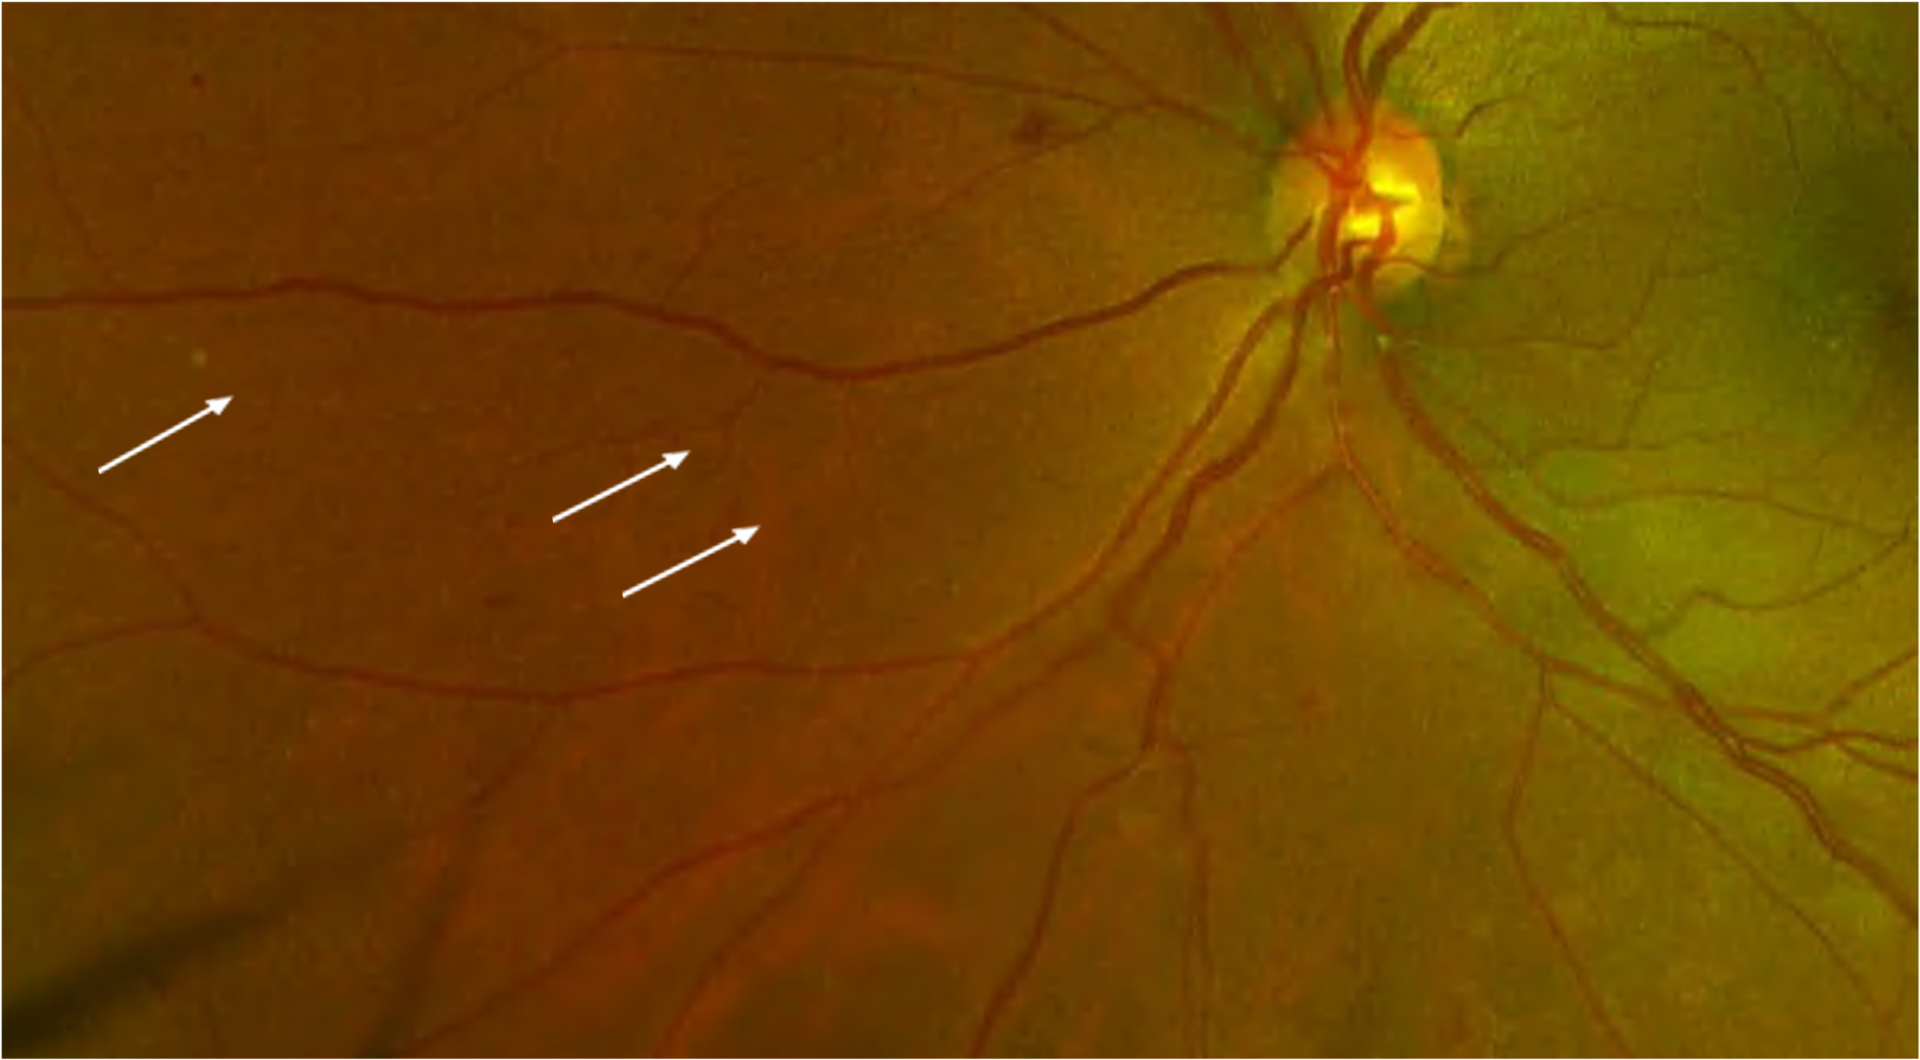

What a beautiful venous beading 🤩 Proliferative diabetic retinopathy

What a beautiful venous beading 🤩 Proliferative diabetic retinopathy Venous Beading Definition Venous loops and venous beading frequently occur adjacent to areas of nonperfusion and reflect increasing retinal ischemia. Venous loops and venous beading: Their occurrence is the most significant predictor of. They reflect increasing retinal ischemia, and their occurrence is the most significant predictor. Based on the severity of retinal vascular lesions, npdr is categorized into mild, moderate, and severe forms.. Venous Beading Definition.

Retinal image that exhibits Venous beading and IRMA caused due to Venous Beading Definition Based on the severity of retinal vascular lesions, npdr is categorized into mild, moderate, and severe forms. Venous loops and venous beading: Their occurrence is the most significant predictor of. Frequently occur adjacent to areas of nonperfusion; Venous loops and venous beading frequently occur adjacent to areas of nonperfusion and reflect increasing retinal ischemia. They reflect increasing retinal ischemia, and. Venous Beading Definition.